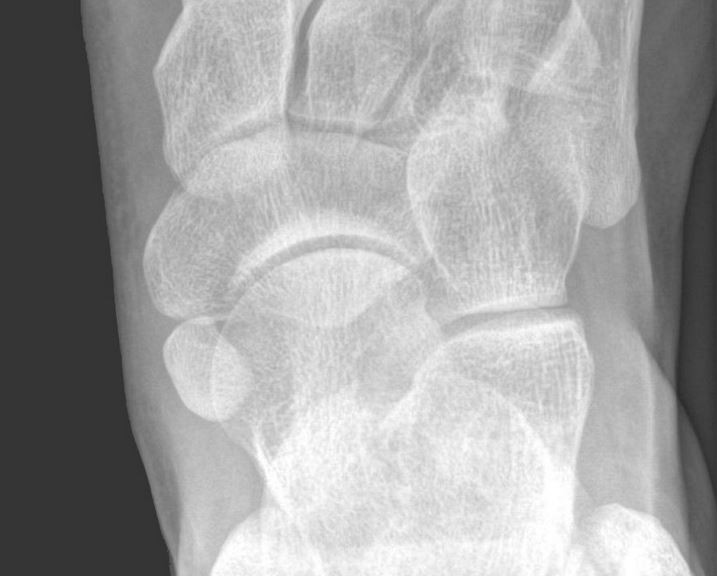

It is unclear what causes this condition, but experts believe that it occurs when the bone and connective tissue develop in the foot in an abnormal manner. The condition can be diagnosed by taking a history of symptoms and performing a complete physical examination. X-rays, CT scans, and MRI may be required to identify the presence of the accessory navicular bone.

A doctor can diagnose accessory navicular syndrome through a physical exam of the foot and ankle. He or she will ask the patient about any symptoms and may gently press on the area to assess for pain and tenderness. An X-ray can confirm the presence of the extra bone, and additional imaging studies like an MRI or CT scan may be required if inflammation is suspected.